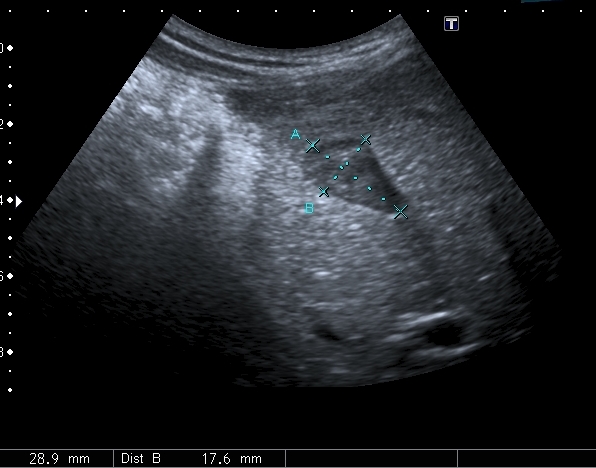

На УЗИ рядом с желчным пузырём определяется овоидное образование солидной струкутры с чёткими контурами.

При ЦДК кровоток в образовании не регистрировался, свободной жидкости в брюшной полости не было.

Порекомендовал КТ, но в связи с наступающими новогодними праздниками и каникулами мальчик уехал домой и появился повторно через 2 месяца без жалоб для контрольного исследования. На УЗИ - картина осталась без динамики

Предположил наличие удвоения желчного пузыря, с этим заключением пациент исчез из поля зрения.